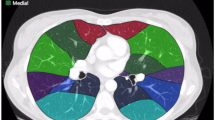

In modern medical applications, computed tomography image is used as one of the most useful tools for diagnosis and localization of lesions. It can provide patients with precise information about the location and size of their tumor lesions. Traditional medical diagnosis is not only very time consuming but also not very accurate. Nowadays, the automatic detection of lesions on computed tomography has become a research area of great interest, and researchers aim to use computer-aided diagnosis to assist in clinical medical diagnosis. However, for current detection algorithms, the accuracy of automatic lesion detection is still low, especially for small lesions. In this paper, to improve the accuracy of detection of small lesions, we propose a Multi-Scale Response Module (MSR) that incorporates global attention into Feature Pyramid Network (FPN) build on backbone. At each pyramid level, the proposed Aggregated Dilation Block (ADB) is used to capture the variations in the fine-grained scales. The response of the network to small lesion features is then reinforced by the Global Attention Block (GAB). We build a Feature Pyramid Network (FPN) based on the highly responsive output of the MSR module, with each layer of the FPN fusing high semantic information from low resolution layers. The experimental results show that our method has a higher detection accuracy with mAP value of 58.4 and a high sensitivity compared to the state-of-the-art methods.